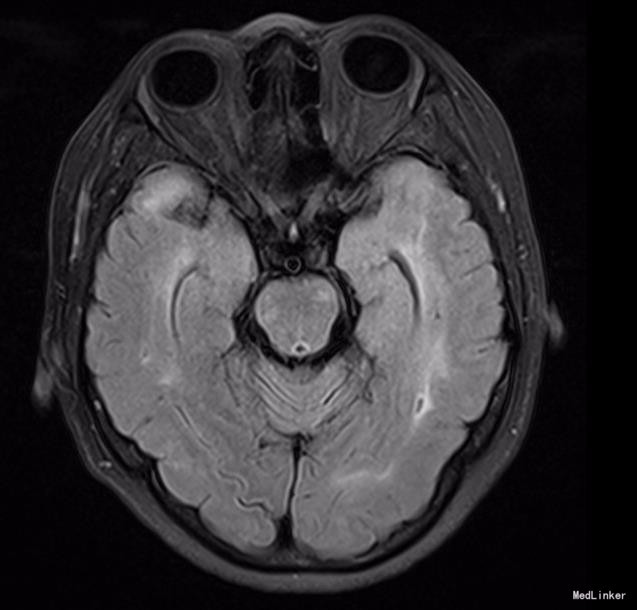

神清,说话吐词清晰。双侧瞳孔等大等圆,眼球运动正常,光反射灵敏,无面舌瘫,颈软。左手握力下降,右下肢轻瘫试验阳性,双上肢腱反射稍高,双侧膝反射亢进,霍夫曼征及内罗里索征阳性。直线行走试验阳性,闭目难立征阴性,双侧指鼻试验阴性。双侧病理征未引出,四肢浅感觉等称。实验室检查未见明显异常。MRI示:脑干、双侧颞极、外囊、额顶叶、放射冠区及丘脑、脑桥异常信号,结合MRS提示符合缺血性改变,部分软化灶形成.结合病变位置(颞极、外囊)及患者年龄,考虑CADASIL可能。头颈血管大致正常,NOTCH3基因见图